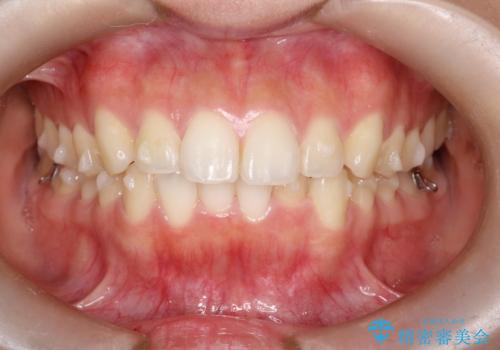

下顎前歯の叢生を短期間で改善

- 患者様は、下顎前歯のガタガタ(叢生)の改善を希望して来院されました。診断の結果、非抜歯で治療可能であると判断し、透明で目立たないインビザラインを使用する矯正治療計画を立案しました。短期間での治療を希望されていたため、IPR(歯間削合)を併用してスペースを確保しながら、効率的に歯を並べることを目指しました。

治療では、インビザラインを用いて計画的に歯を移動させ、短期間での歯列改善を実現しました。IPRを行うことで、抜歯をせずに必要なスペースを確保し、歯列全体を整えました。治療中は、装置の適切な装着時間を守ることが重要であり、患者様にも継続的な協力をお願いしました。また、歯肉や歯根への負担を最小限に抑えるため、歯の移動を慎重に管理しました。結果として、短期間で下顎前歯の叢生を改善し、自然な見た目と機能性を兼ね備えた歯列を実現できました。